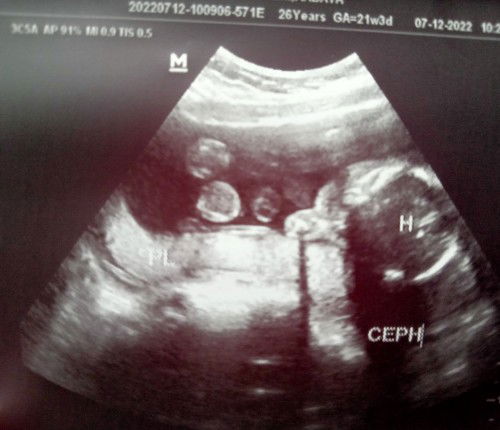

Hindi pa alam ang gender

Hi mga mommies ito yung baby ko 5 months na sya sa tummy ko at super excited na kami ng daddy nya na malaman yung gender nya kaso ayaw nya bumukaka kahit inalog alog na. Naranasan nyo rin ba yung ganito?#1stimemom